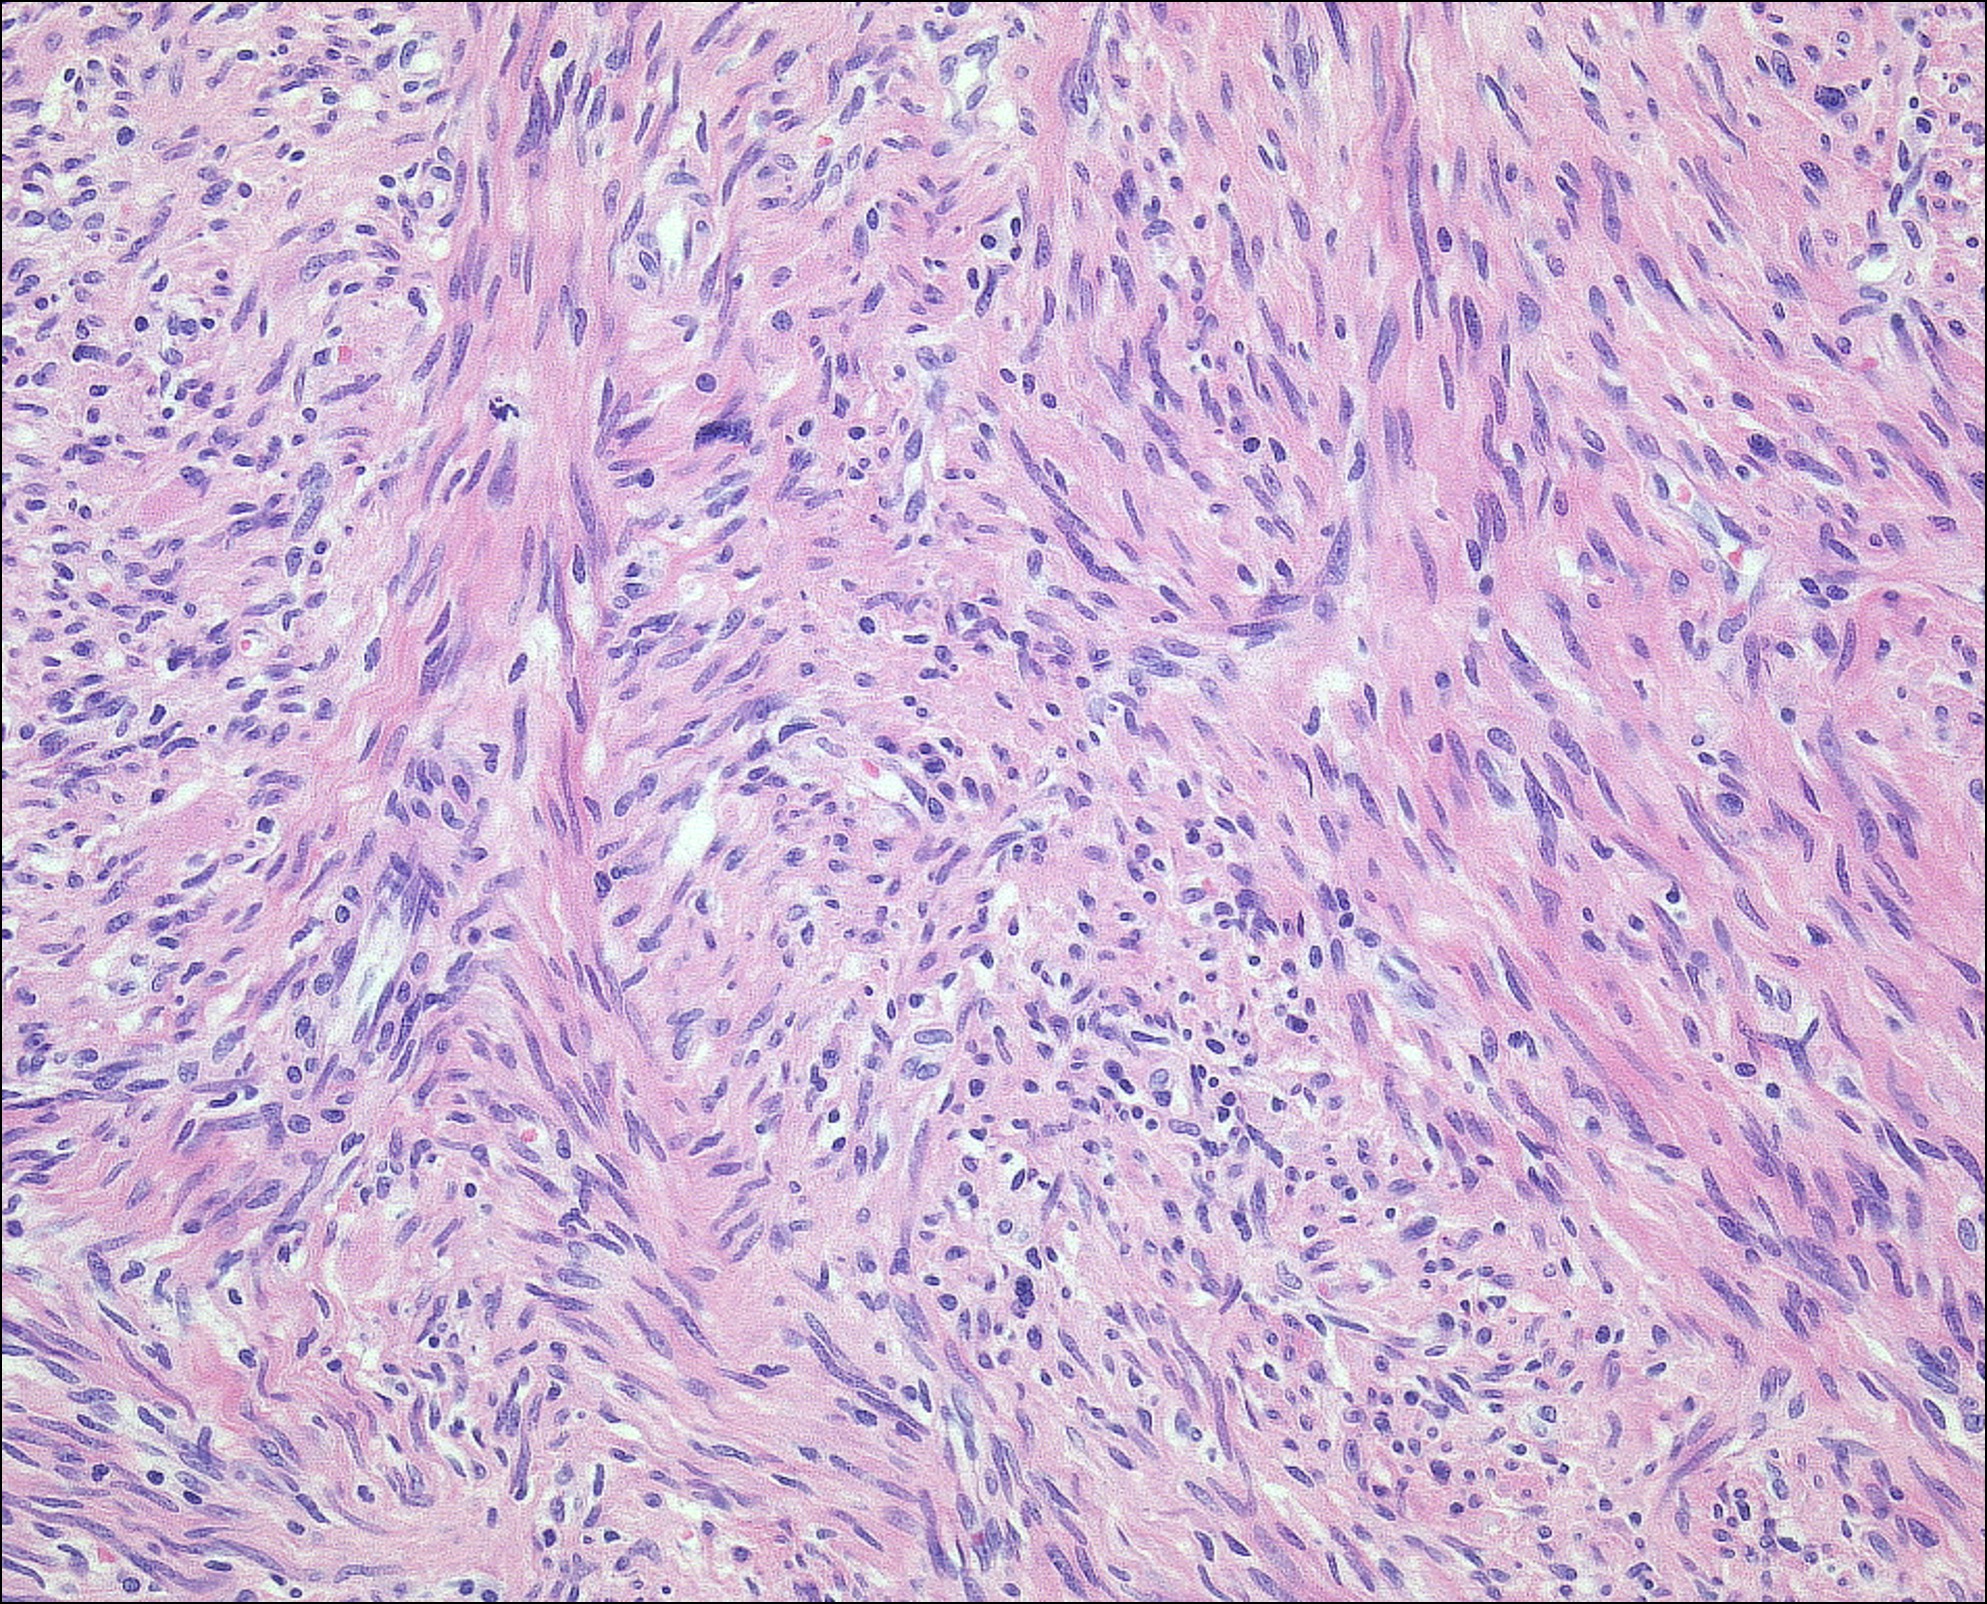

1) Fasciite proliférative

2) Patients adults ou agés, plus rare que fasciite nodulaire, sous cutané (fascite proliférative) ou musculaire (myosite proliférative)

3)

Mal délimité

Prolifération de cellules fusiformes et de cellules ganglion-like

Mitoses fréquentes mais pas atypiques

Le long des fascia sous-cutané ou des fibres musculaires

4)

Cellules fusiformes = SMA+

Cellules ganglion like = négatives